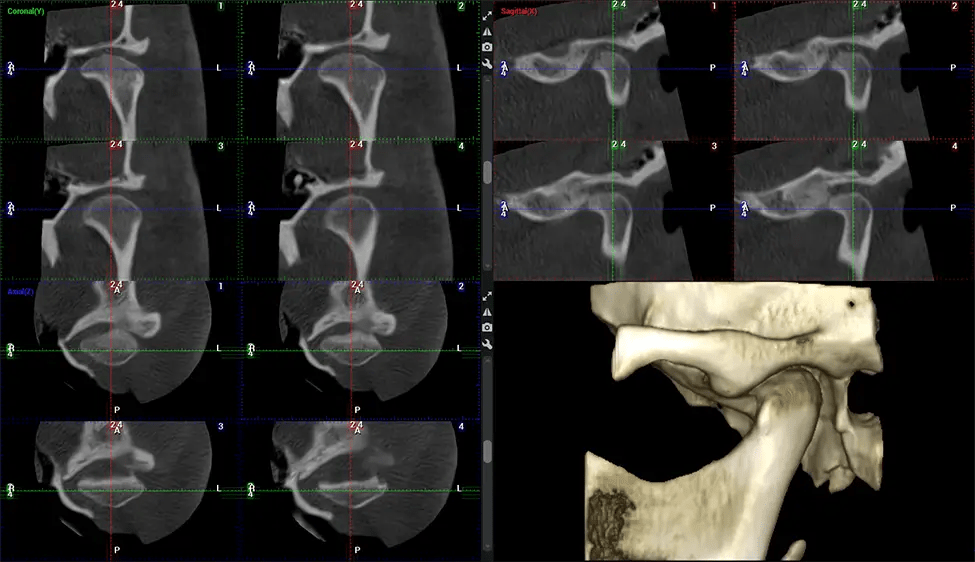

Cirujano Oral y Maxilofacial Cirugías orales complejas, cirugía ortognática (de mandíbula) y extracción de dientes impactados. Ofrece una visualización tridimensional precisa del cráneo, la mandíbula y la unión craneocervical para mejorar la precisión del diagnóstico y minimizar los riesgos quirúrgicos.

Quiropráctico cervical superior Diagnóstico de problemas estructurales en las vértebras C1-C2, evaluación de desalineación e inestabilidad y evaluación del dolor crónico. Permite vistas precisas y con carga de la columna cervical superior, lo que ayuda a identificar anomalías que fundamentan terapias específicas y no invasivas.

Planmeca Viso G7 CBCT La tomografía computarizada de haz cónico (CBCT) está diseñada para superar las exigencias de los líderes de la industria, los especialistas y las grandes instituciones. Cuenta con un sensor de gran tamaño (25 × 30 cm) con cuatro cámaras integradas. Puede capturar tamaños de volumen ilimitados, desde ø3×3 cm hasta ø30x30cm, capturando el casquete escutelario a través de C7 en la columna cervical. Planmeca Viso G7 ofrece el escaneo de volumen único más grande de la industria de ø30×19 cm. Está preparado para manejar modalidades de imágenes avanzadas como la tecnología Planmeca ProFace® y Planmeca 4D™ Jaw Motion. El soporte occipital para la cabeza permite una visión sin obstáculos del tejido facial.